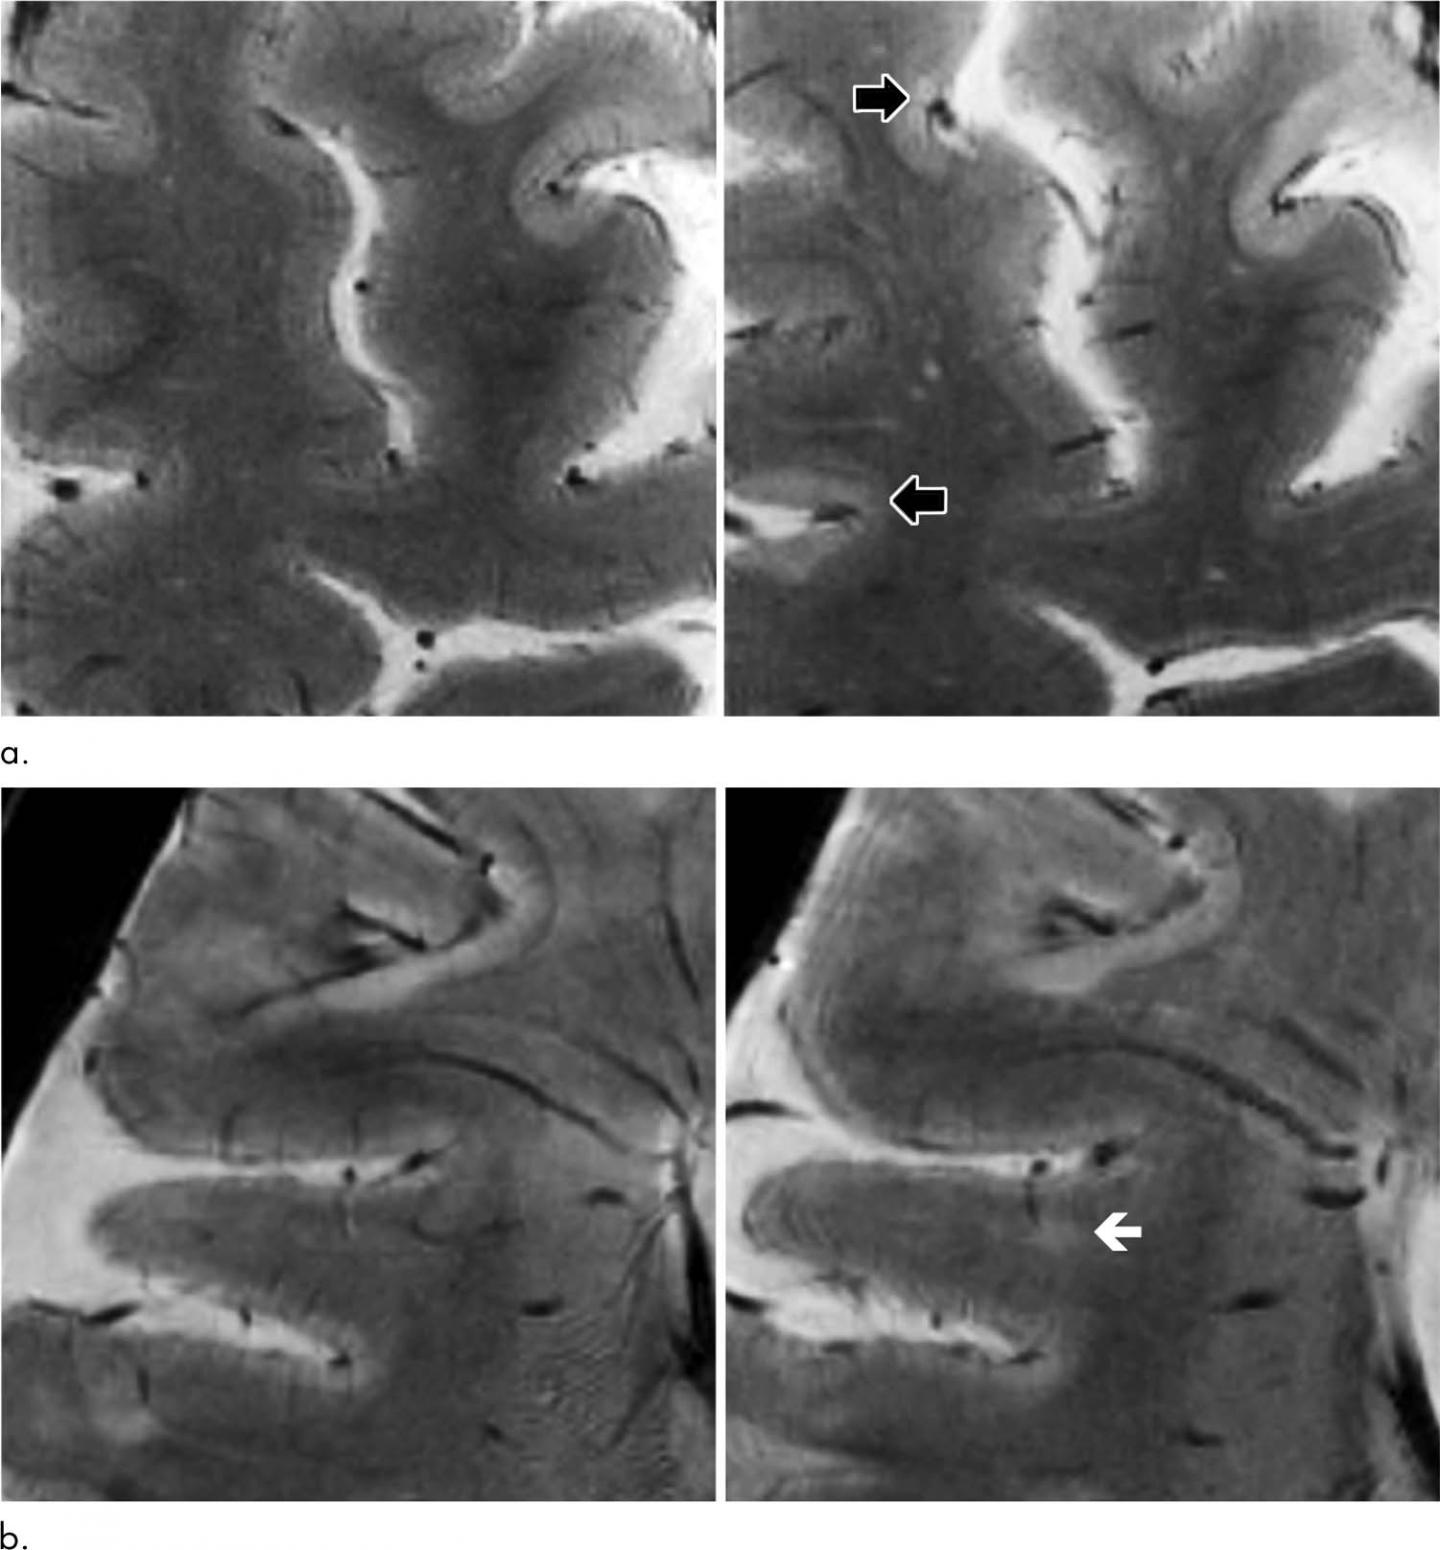

Reduced Diffusion in a Subset of Acute MS Lesions A Serial Ms Progression Mri traditional mri biomarkers do not adequately track progressive ms. learn about the clinical, pathological and radiological features of multiple sclerosis (ms), a chronic. learn about the types, causes, and measures of progression in multiple sclerosis (ms), a disease of the central nervous system. this study evaluates the effectiveness of conventional mri in predicting disability, cognitive decline,. Ms Progression Mri.